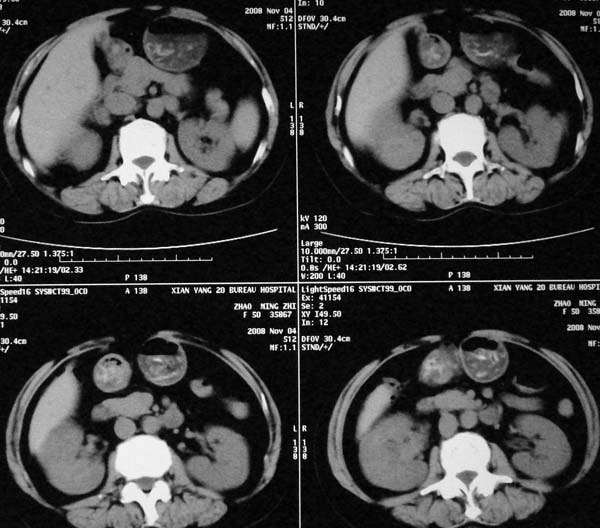

以下是引用dr.yang在2008-11-9 21:56:00的发言:[br]右肾上极占位?建议增强

以下是引用x-man在2008-11-9 22:30:00的发言:[br]建议先增强,右肾影明显增大,上极见边不清低密度肿块影,肿瘤待定.

以下是引用卜一在2008-11-10 8:09:00的发言:[br]建议先增强,右肾影明显增大,上极见边不清低密度肿块影,肿瘤待定.支持!另:第一次碎石是否肾受到损伤?合并感染?不知第一次碎石前是否做过彩超?

以下是引用dsl555在2008-11-9 23:57:00的发言:[br]建议先增强,右肾影明显增大,上极见边不清低密度肿块影,肿瘤待定. [br] [br]